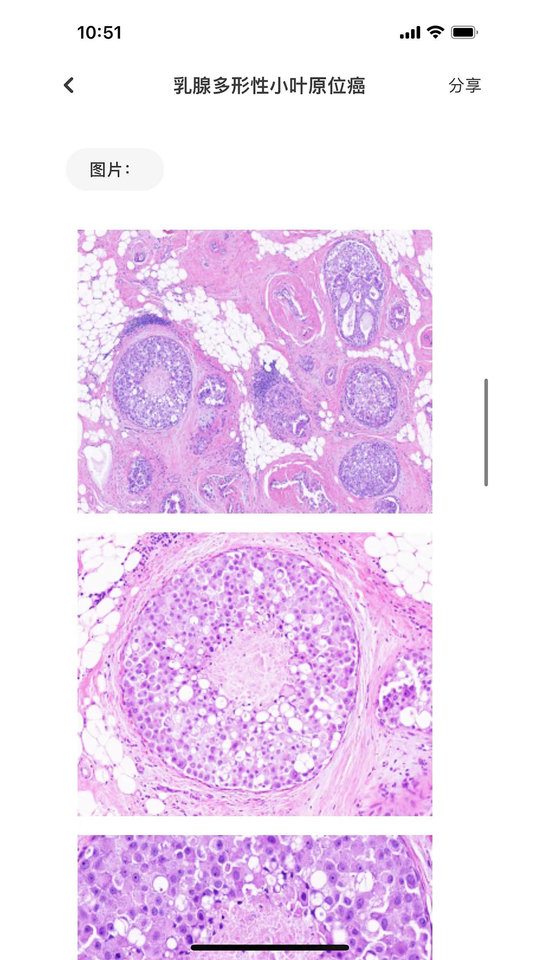

大伽病理是一个为专业病理医师、临床肿瘤医生及相关从业人员提供病理诊断信息查询工具.专注服务病理诊断领域专业用户,最全面的病理诊断交流优质社区.

- 全面专业的病理知识库:

2200+ 病理诊断与鉴别诊断知识库、400+ 免疫组化抗体应用介绍、800+ 肿瘤免疫表型介绍等